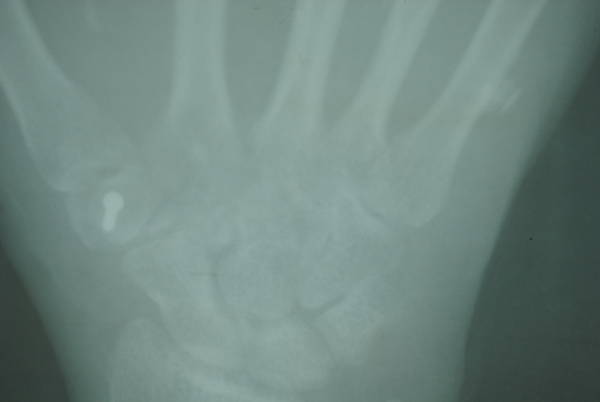

混凝土高压灌注伤

术后15日,皮瓣成活,复查x片豌豆骨游离移植修复大多角骨大部缺损位置良好。